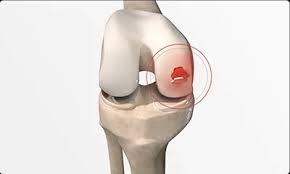

무릎 연골 손상 증상과 동반 증상

무릎 연골 손상 증상은 단순한 무릎 통증으로 끝나지 않고 다양한 동반 증상과 함께 나타납니다. 일반적으로 무릎 부위의 붓기와 불편함이 동반되며, 특히 무릎의 안쪽이나 바깥쪽에서 통증이 느껴질 수 있습니다. 또한, 무릎을 움직일 때 '잠김 현상'이 발생하기도 하며, 이는 무릎 연골 손상 증상이 심한 경우 나타나게 됩니다. 이러한 증상들은 운동 후나 오랜 시간 앉아 있다가 일어날 때 더욱 심해질 수 있습니다.